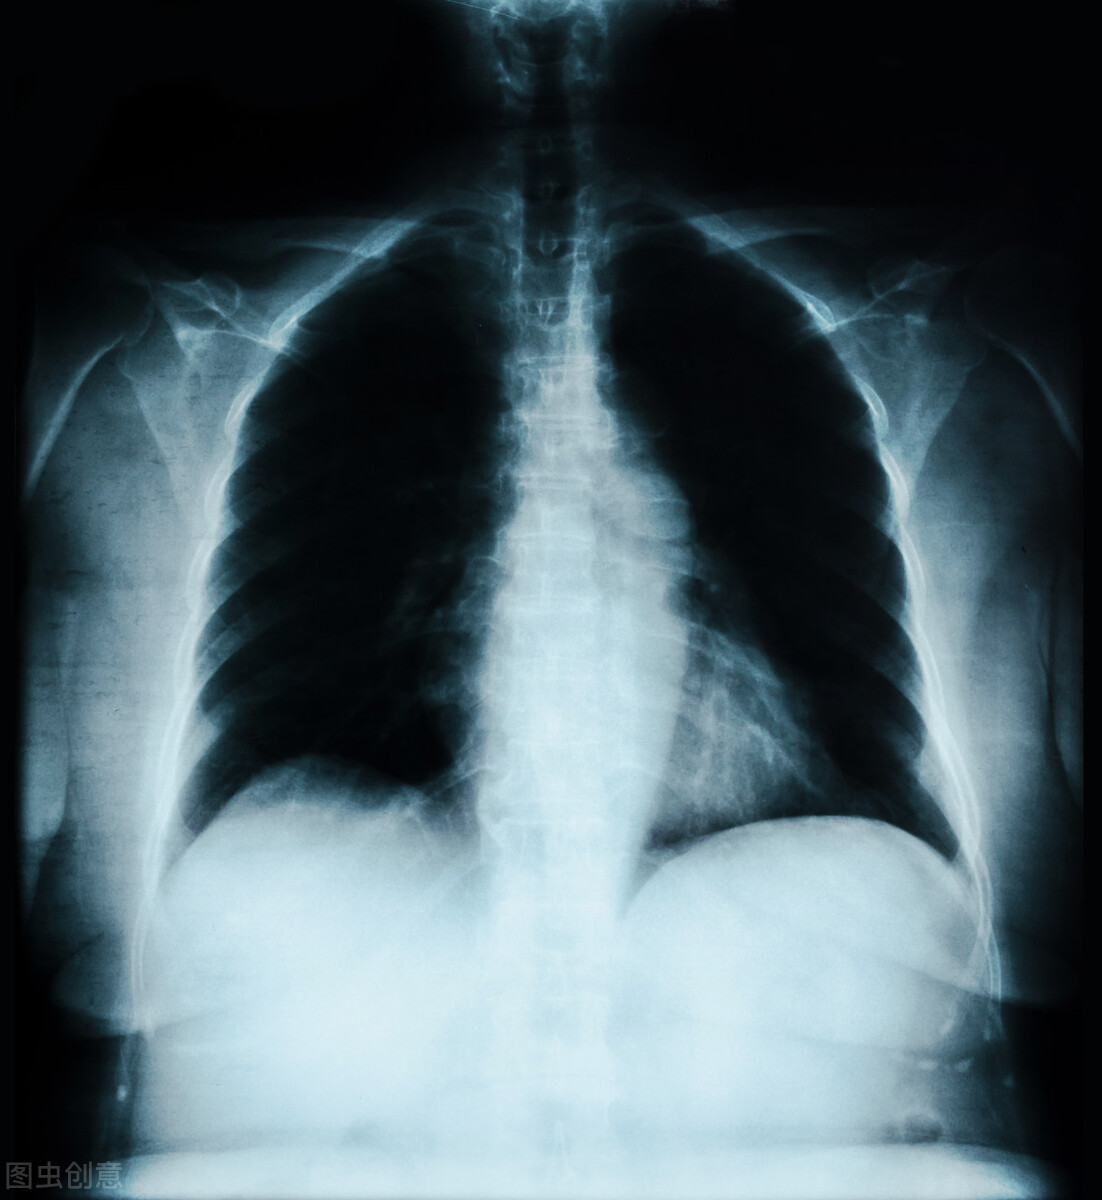

肺部感染是慢性支气管炎急性发作、急性支气管炎、肺炎、支气管扩张感染等肺部感染性疾病的总称,主要是指下呼吸道的感染 。肺部感染根据感染地点的不同,可以分为社区获得性肺炎和医院获得性肺炎,下面分别介绍二者的症状表现。